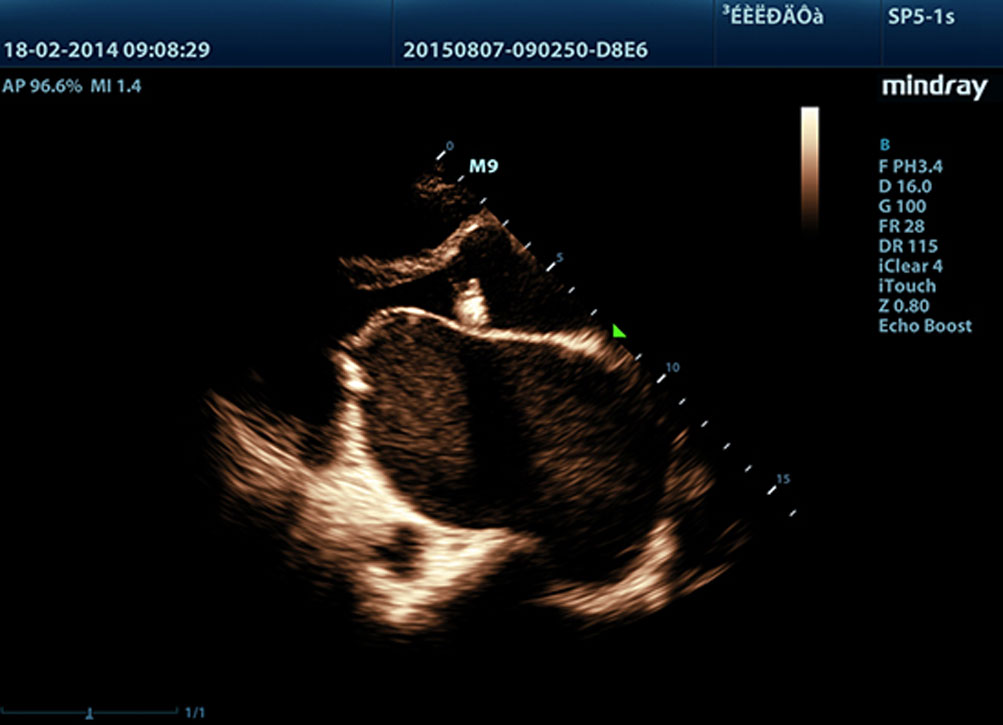

LVO per ecocardiografia sotto stress

Le eccezionali capacit├Ā di M9 consentono lŌĆÖopacizzazione LV durante lo stress, migliorando distinzione tra tessuto miocardico e ristagno di sangue, fornendo una migliore visualizzazione della superficie endocardica. La funzione Stress Echo di M9 comprende un pacchetto completo per lo stress farmacologico e da sforzo. Il pacchetto ├© supportato da un sistema flessibile di rapporto che pu├▓ essere ottimizzato sulle esigenze individuali.